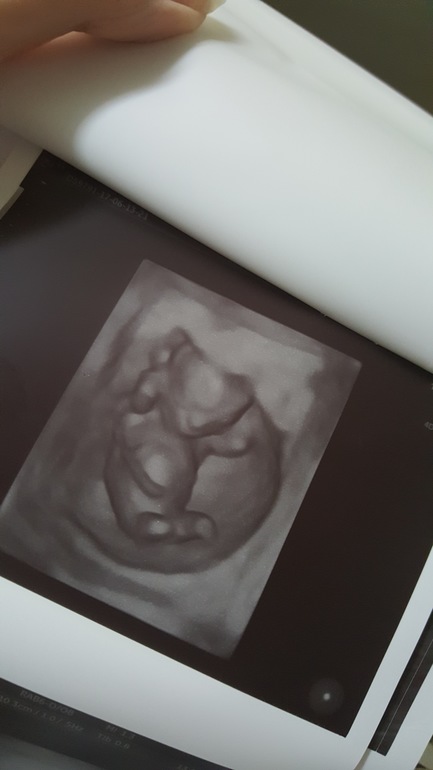

Узи 14 недель (13,3 по М)

Померили нас сегодня основательно аж на 1,5 листах с обоих сторон. Так как мы по сроку уже 14 недель...узи уже 2 триместра.

Ктр не мерили, мерили вес....и так мы приблизительно - 100 грамм!

Еще раз подтвердили девочку!

Наши фото